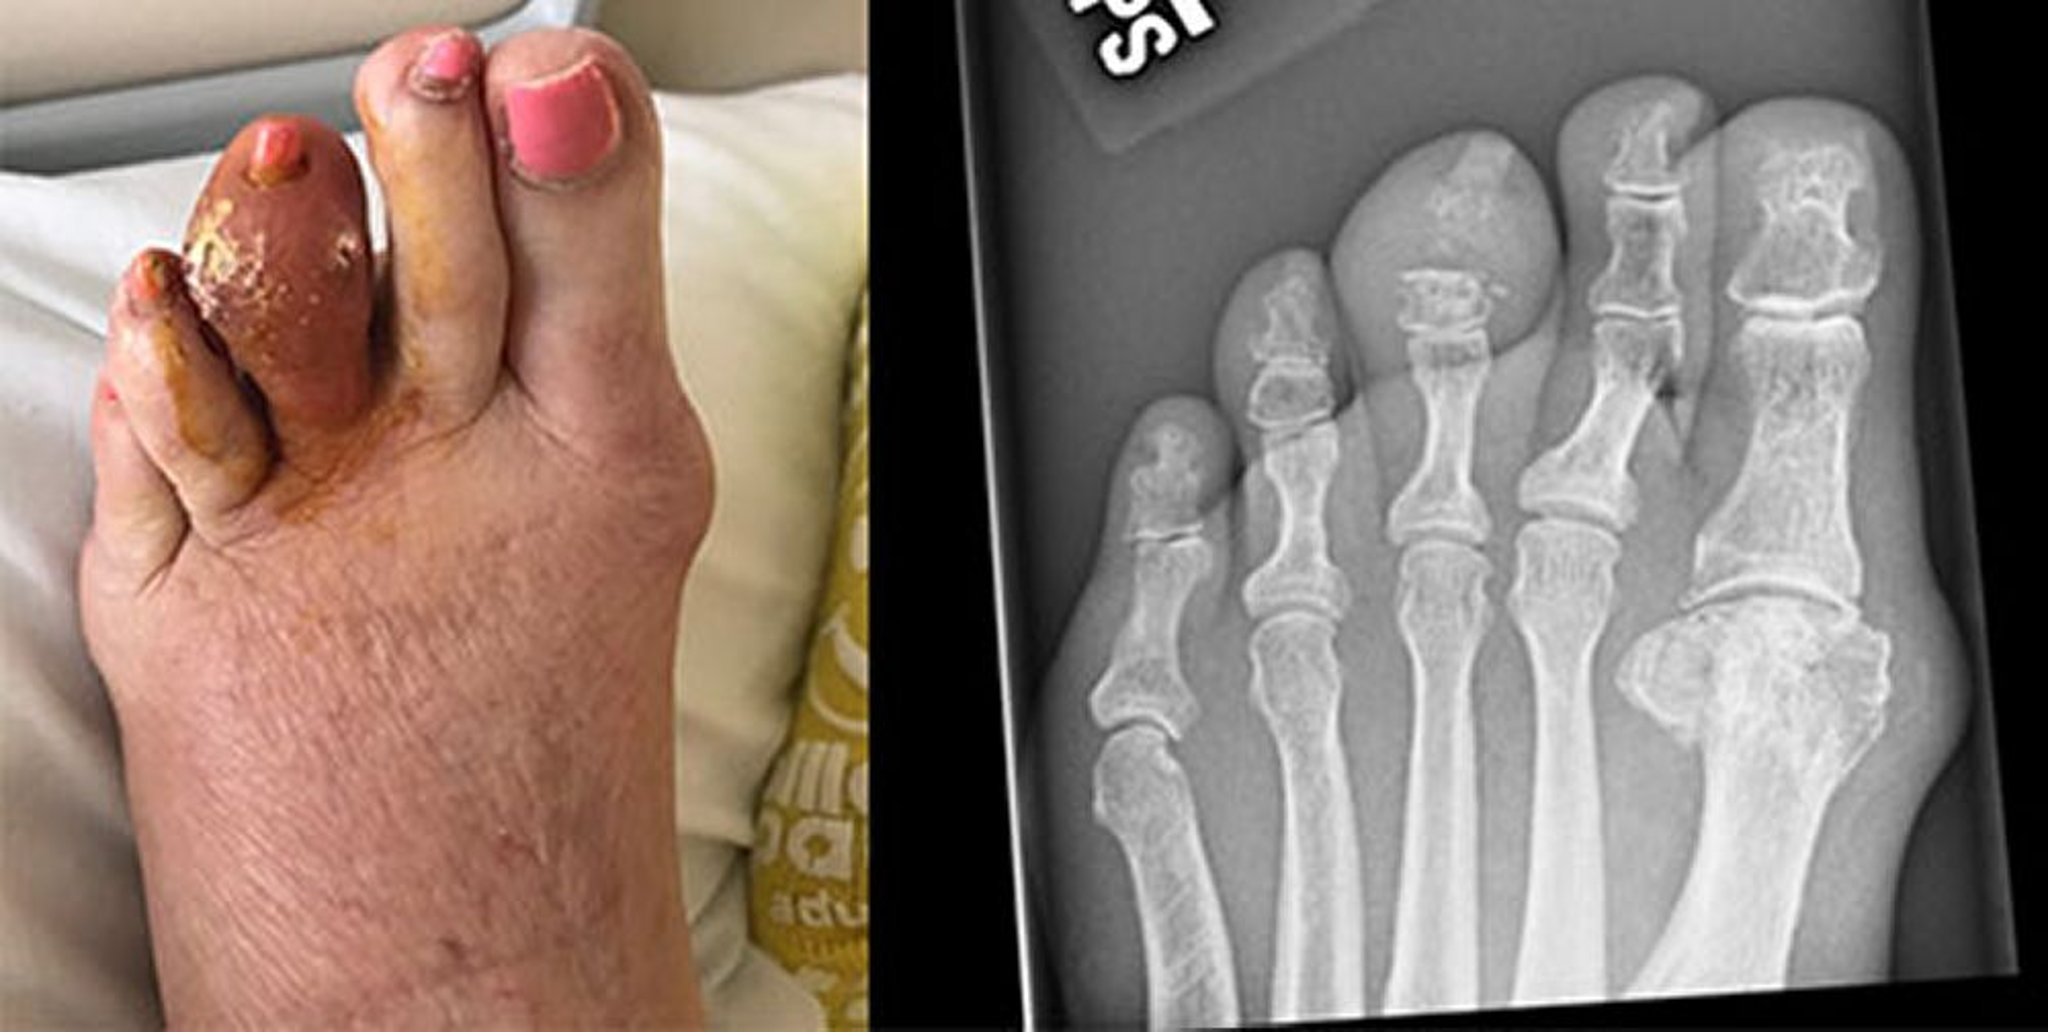

Goutte de l'orteil moyen

Cette photo montre un gros tophus du 3e orteil gauche, qui s'est décomposé et a libéré de l'acide urique durci. La radiographie de droite montre l'érosion de la phalange moyenne et l'articulation interphalangienne distale.

Images courtesy of Brian F. Mandell, MD.